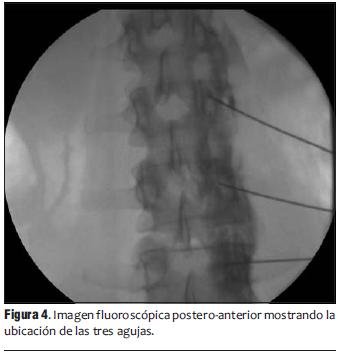

Se inyectó contraste no iónico (Iopamidol 300 mg/ml) 0,5-1 ml, observando en tiempo real su difusión en forma de línea compacta en el borde vertebral anterior por delante del músculo psoas bajo visión lateral (figura 2) y su característica distribución en visión postero-anterior (figura 3).

Se ubicó una aguja a nivel del tercio inferior de L2, una segunda aguja en el tercio superior de L3 y la tercera aguja en el tercio medio de L4 (figura 4).